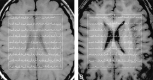

Background and purpose: The new 3.0-T imagers theoretically yield double the signal-to-noise ratio (SNR) and spectral resolution of 1.5-T instruments. To assess the possible improvements for multivoxel 3D proton MR spectroscopy (1H-MRS) in the human brain, we compared the SNR and spectral resolution performance with both field strengths.

Methods: Three-dimensional 1H-MRS was performed in four 21-29-year-old subjects at 1.5 and 3.0 T. In each, a volume of interest of 9 x 9 x 3 cm was obtained within a field of view of 16 x 16 x 3 cm that was partitioned into four (0.75-cm-thick) 16 x 16-voxel sections, yielding 324 (0.75-cm3) signal voxels per examination.

Results: In an acquisition protocol of approximately 27 min, average voxel SNRs increased 23-46% at 3.0 versus 1.5 T in the same brain regions of the same subjects. SNRs for N-acetylaspartate, creatine, and choline, respectively, were as follows: 15.3 +/- 4, 8.2 +/- 2.2, and 8.0 +/- 2.0 at 1.5 T and 22.4 +/- 7.0, 10.1 +/- 3.5, and 10.1 +/- 3.6 at 3.0 T. Spectral resolution (metabolite linewidths) were 3.5 +/- 0.5 Hz at 1.5 T versus 6.1 +/- 1.5 Hz at 3.0 T in approximately 900 voxels. Spectral baselines were noticeably flatter at 3.0 T.

Conclusion: Expected gains in SNR and spectral resolution were not fully realized in a realistic experiment because of intrinsic and controllable factors. However, the 23-46% improvements obtained enable more reliable peak-area estimation and an 1H-MRS acquisition approximately 50% shorter at 3.0 versus 1.5 T.